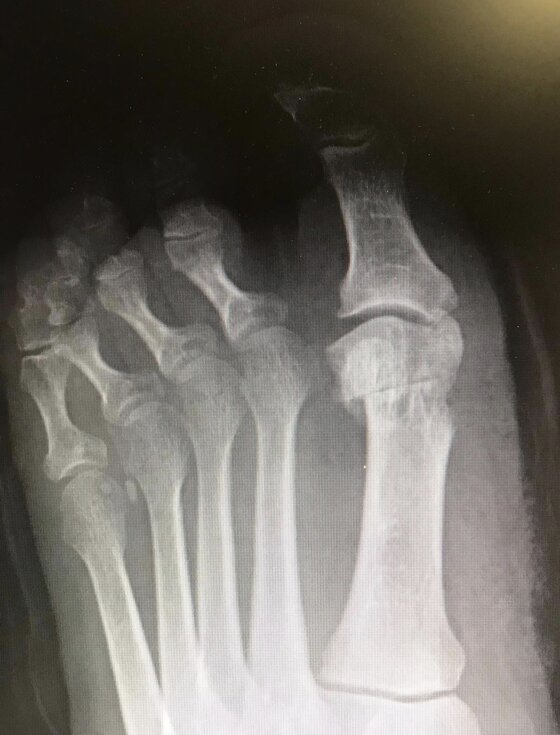

Radiografie post-operatorie in AP e LL di intervento di correzione di Alluce Valgo con tecnica mini-invasiva senza utilizzo di mezzi di sintesi metallici. Per l’osteotomia di correzione del I MT ho utilizzato un pin riassorbibile che quindi non è visulizzabile alle radiografie, mentre per l’osteotomia della prima falange del primo dito non ho utilizzato alcun mezzo di sintesi

Radiografie post-operatorie in AP di due interventi di correzione di Alluce Valgo con tecnica mini-invasiva senza utilizzo di mezzi di sintesi metallici. Per l’osteotomia di correzione del I MT ho utilizzato in entrambi i casi un pin riassorbibile che quindi non è visulizzabile alle radiografie. Nel caso a sinistra per l’osteotomia della prima falange del primo dito non ho utilizzato alcun mezzo di sintesi, nel caso a destra non ho effettuato l’osteotomia in quanto era presente un alluce valgo meno grave